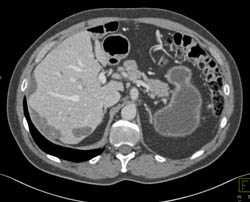

Diagnosis

Subcapsular Fluid